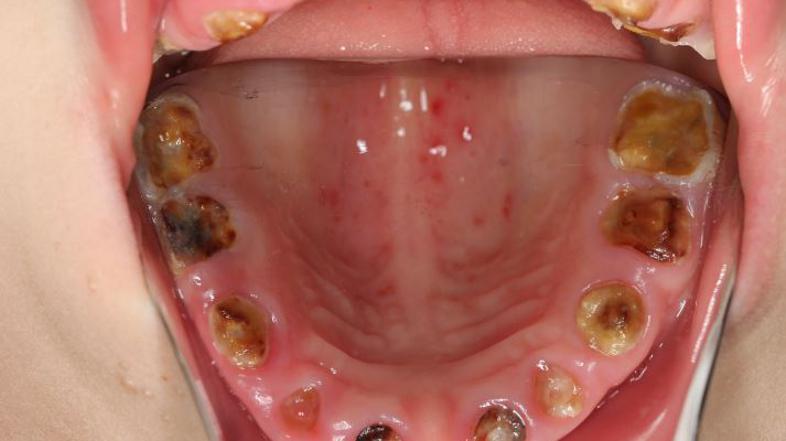

Gnili zobje UKCLJ

"Imeli smo leto in pol staro deklico, ki smo ji izpulili vse zobe, ki jih je lahko imela takrat v ustih,"  je na novinarski konferenci, kjer so zobozdravniki lani pozvali k prenovi sistema zobozdravstvene preventive dejala Tanja Tomaževič s centra za otroško in preventivno zobozdravstvo na stomatološki kliniki.

Strokovnjakinja je dodala, da je tako majhne otroke zelo težko zdraviti. "Dobimo otroka, ki je star dobro leto, ali v tretjem letu starosti. Ker vemo, da ni sposoben sodelovati z nami, da ne razume, da mu je treba popraviti zobek, ga bi bilo treba prijeti in narediti na silo, česar si ne želimo, sploh če je treba popraviti več zob. Zato že tako majhni potrebujejo poseg in to pri splošni anesteziji,"  je povedala Tomažičeva, ki v teh dneh znova opozarja starše, naj bodo pazljivi kaj pojedo in predvsem pijejo njihovi otroci.

Takšne otroke je zelo težko zdraviti

Po besedah stomatologinje, se sprva na zobeh pokažejo bele lise, ki so posledica izgube mineralov iz sklenine. Če bolezen napreduje, je zob treba zdraviti, pri napredovani bolezni pa mlečne zobe večinoma odstraniti.  Če napreduje v dentin, se zdravi s plombami. Če bolezen napreduje še naprej do pulpe in je razširjena že preko pulpe v kost, je treba tak zob endodontsko zdraviti, mlečnega pa večinoma odstraniti, pojasnjuje in dodaja. "Otrok, ki ima karies, do četrtega, petega leta ne razume, da je obisk zobozdravnika zanj dober. S temi otroki je zelo težko delati, ker jim je težko pojasniti, da bodo dobili lokalno anestezijo “komarčka”, da jih ne bi bolelo, hkrati pa je njihova pozornost zelo kratkotrajna."